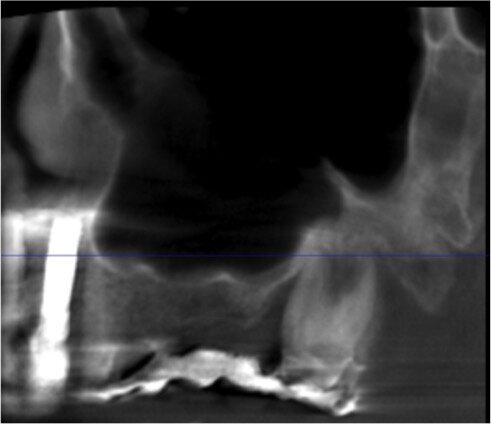

La paziente, di sesso femminile e con anamnesi medica negativa, si presenta in visita lamentando mobilità della protesi fissa presente nel II quadrante. Dopo l’esame obiettivo e strumentale gli elementi 23 e 27 (pilastri di ponte) vengono reputati non mantenibili e si programma l’estrazione degli stessi. Contestualmente all’estrazione si pianifica, con lo studio della CTCB pre-operatoria, l’inserimento di 3 impianti e la futura riabilitazione implanto-protesica fissa con pilastri di ponte 23-24-25. L’altezza di cresta residua è circa di 4/5 mm in altezza per le tre sedi (Figg. 1-4). La paziente riceve una profilassi antibiotica di tipo Short-term (Amoxicillina + Acido Clavulanico 2 g 1 ora prima dell’intervento) e fa uno sciacquo di 1 minuto con CHX 0,2% prima della chirurgia.

Fig. 1 - Sezione panorex CTCB pre-operatoria II quadrante con visione del seno mascellare.

Fig. 2 - Cross section di zona 23.

Fig. 3- Cross section di zona 24.

Fig. 4 - Cross section di zona 25.